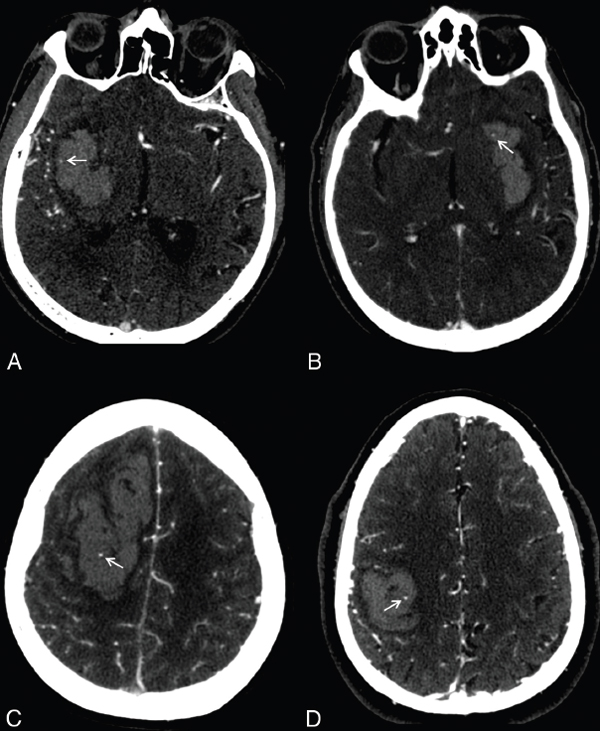

点征(spot sign)在临床上用的比较多,是以碘对比剂外渗作为标记物预测

insular ribbon sign(岛带征) 2019-02-02 09:22 关注 点赞

【讲座】医学影像征象解析汇集(神经系统部分)